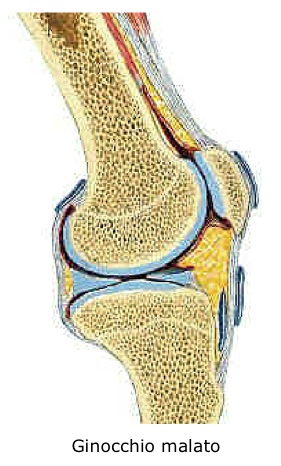

Uno dei principali motivi del dolore deriva dalla perdita della normale congruenza delle superfici articolari, con abrasioni a carico del rivestimento cartilagineo, la cui funzione è proprio quella di rendere levigate e scorrevoli tali superfici.

Molteplici patologie possono condurre a tale situazione: la più comune e frequente è l’artrite in senso lato, che comprende sia le forme a probabile origine meccanica (conseguenti ad alterazioni strutturali congenite), sia le forme degenerative (gonartrosi idiopatica), sia le forme acquisite (necrosi ischemiche, traumi, osteoporosi, ecc.). Altre frequenti cause sono le artriti infiammatorie (artrite reumatoide, psoriasica, ecc.).

Un’articolazione è assimilabile ad un giunto meccanico che permette a due parti ossee rivestite di cartilagine di ruotare o scorrere l’una sull’altra.

L’articolazione del ginocchio in particolare consente una notevole motilità congiunta ad un altrettanto ragguardevole solidità.